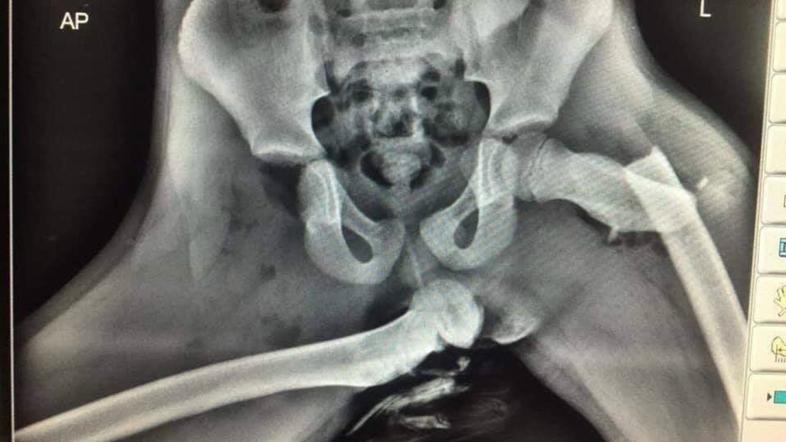

Rentgenski posnetek noge na armaturki Reševalni pas/Twitter

Šokantna rentgenska fotografija izpahnjene stegnenice, posledica nespametnega početja.

Sopotnikova desna noga je bila zaradi nesreče povsem iztaknjena iz kolka in je dobesedno predrla kožo. Sunek ob nesreči je bil tako močan, da je hkrati levo stegnenico grdo prelomilo.